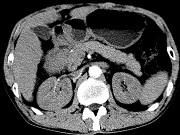

问题 女,63岁,右上腹疼痛,呈不规律性钝痛,伴恶心,时有呕吐,呕吐物为胃内容物混有胆汁,CT检查如图,最可能的诊断是()

选项 A.十二指肠克罗恩病 B.十二指肠结核 C.十二指肠癌 D.十二指肠淋巴瘤 E.十二指肠平滑肌瘤

答案 C